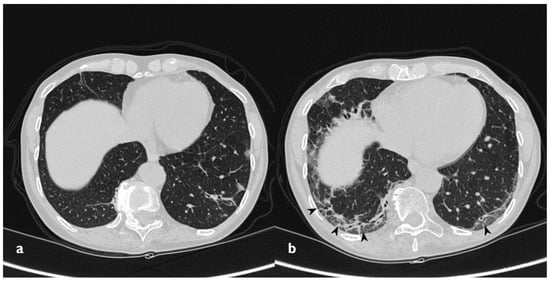

Figure 10. On the left (a): baseline HRCT; left parenchymal consolidations with air bronchogram sign in the context (arrowheads). On the right (b): HRCT after steroid treatment; new ground-glass areas (arrowheads) have appeared in the site of consolidations.

3.3. Ground Glass

Ground-glass opacities completely disappeared in nine out of 15 patients that have shown this pattern at baseline HRCT. In two patients, new ground-glass areas appeared where a previous consolidation was present, like residual components of the consolidations (Figure 10) (Table 6).